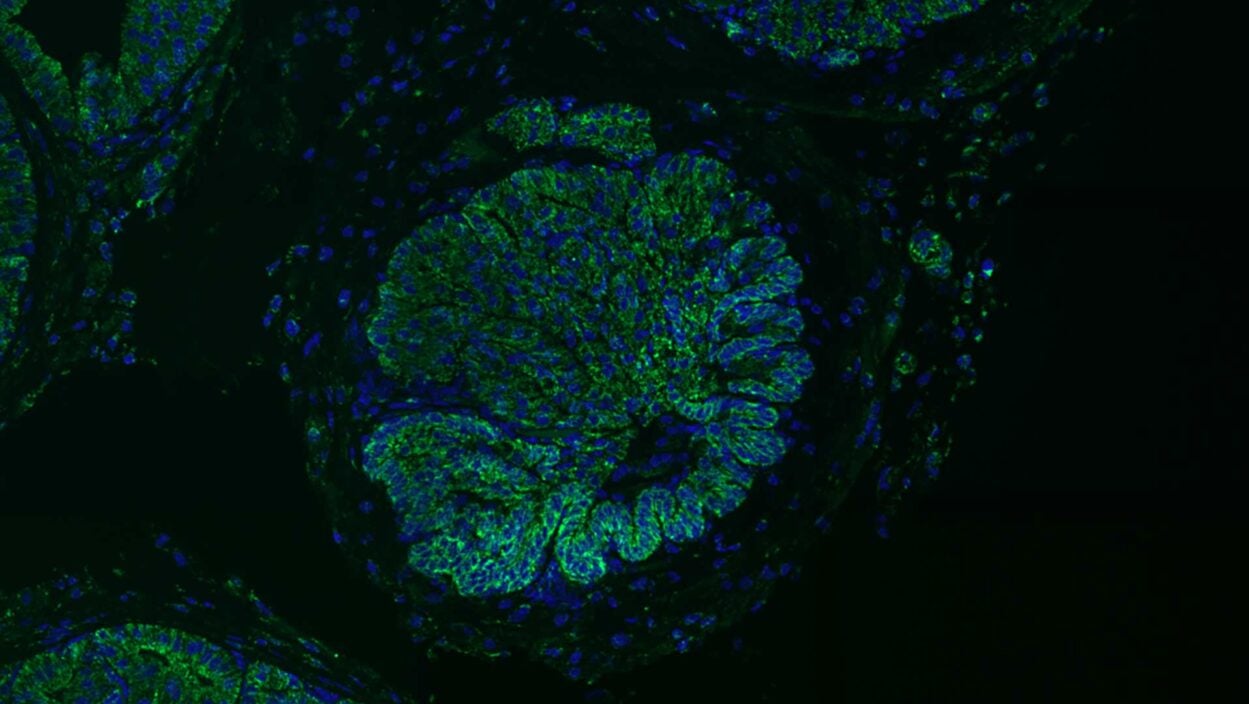

An angry peacock is no joke. Like the colorful bird and its tall tail feathers, cancer biology can make for some eye-catching images. Read the story »